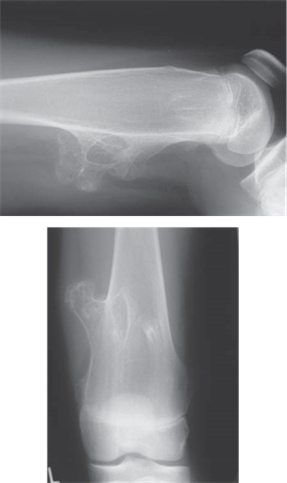

Describe what you see on these radiographs. What do you think is the most likely diagnosis?

When describing bone lesions remember: age; bone; site; matrix; margin; periosteal reaction; soft tissue mass; likely diagnoses.

The radiograph shows a lesion arising from the distal femoral metaphysis in a skeletally mature patient

The matrix of the lesion is mostly sclerotic, suggesting osteoblastic (bone-forming) activity; there are also a few small lytic (bone destruction) areas

The margins of the lesion are not clearly defined with a broad zone of transition into the surrounding bone

The cortex of the bone overlying the lesion is poorly defined and has been invaded by the lesion

The periosteum has been elevated anteriorly (Codmanโ€™s triangle) and there is an associated โ€˜sunburstโ€™ spiculation appearance

The lesion appears to have expanded out into the surrounding soft tissues

These features suggest that this is an aggressive, fast-growing, osteoblastic lesion of the distal femur โ€” the most likely diagnosis would be an osteosarcoma.